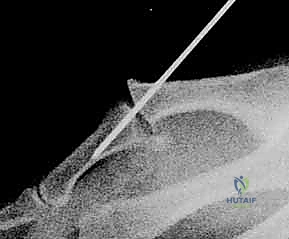

3. الرنين المغناطيسي (MRI) والموجات فوق الصوتية (Ultrasound)

لتقييم الأنسجة الرخوة والأربطة بدقة متناهية، يتم اللجوء للرنين المغناطيسي. هذا الفحص حاسم جداً لاكتشاف ما يُعرف بـ آفة ستينر (Stener Lesion).

ما هي آفة ستينر (Stener Lesion)؟

تحدث هذه الحالة المعقدة عندما يتمزق الرباط الجانبي الزندي (UCL) بالكامل، وبدلاً من أن يبقى في مكانه ليلتئم، ينزلق الرباط الممزق ويصبح محاصراً فوق وتر عضلة أخرى (وتر العضلة المقربة للإبهام). هذا التداخل الميكانيكي يمنع التئام الرباط بشكل طبيعي تماماً، ويجعل التدخل الجراحي أمراً حتمياً لا مفر منه.